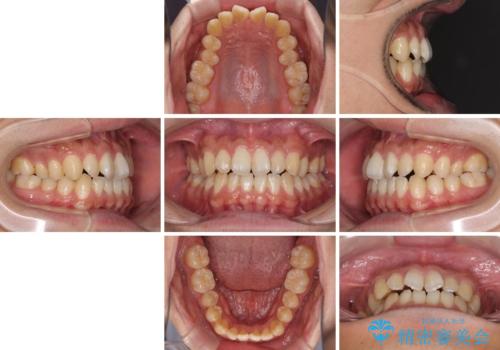

下顎前歯と上顎の部分矯正

- 上下の前歯の叢生を気にして来院された患者様です。

前歯のみの矯正治療を希望でしたが、上顎臼歯が舌側転位していたため、上顎は全体を、下顎は前歯のみを矯正治療することとしました。

矯正治療は上下全顎を行うことが大前提ですが、費用などの点から、今回は部分矯正を選択することとなりました。

患者様本人は咬みにくさを感じていないようですが、部分矯正は咬み合わせの改善が困難であることが多く、咬みにくさが残ることがあります。